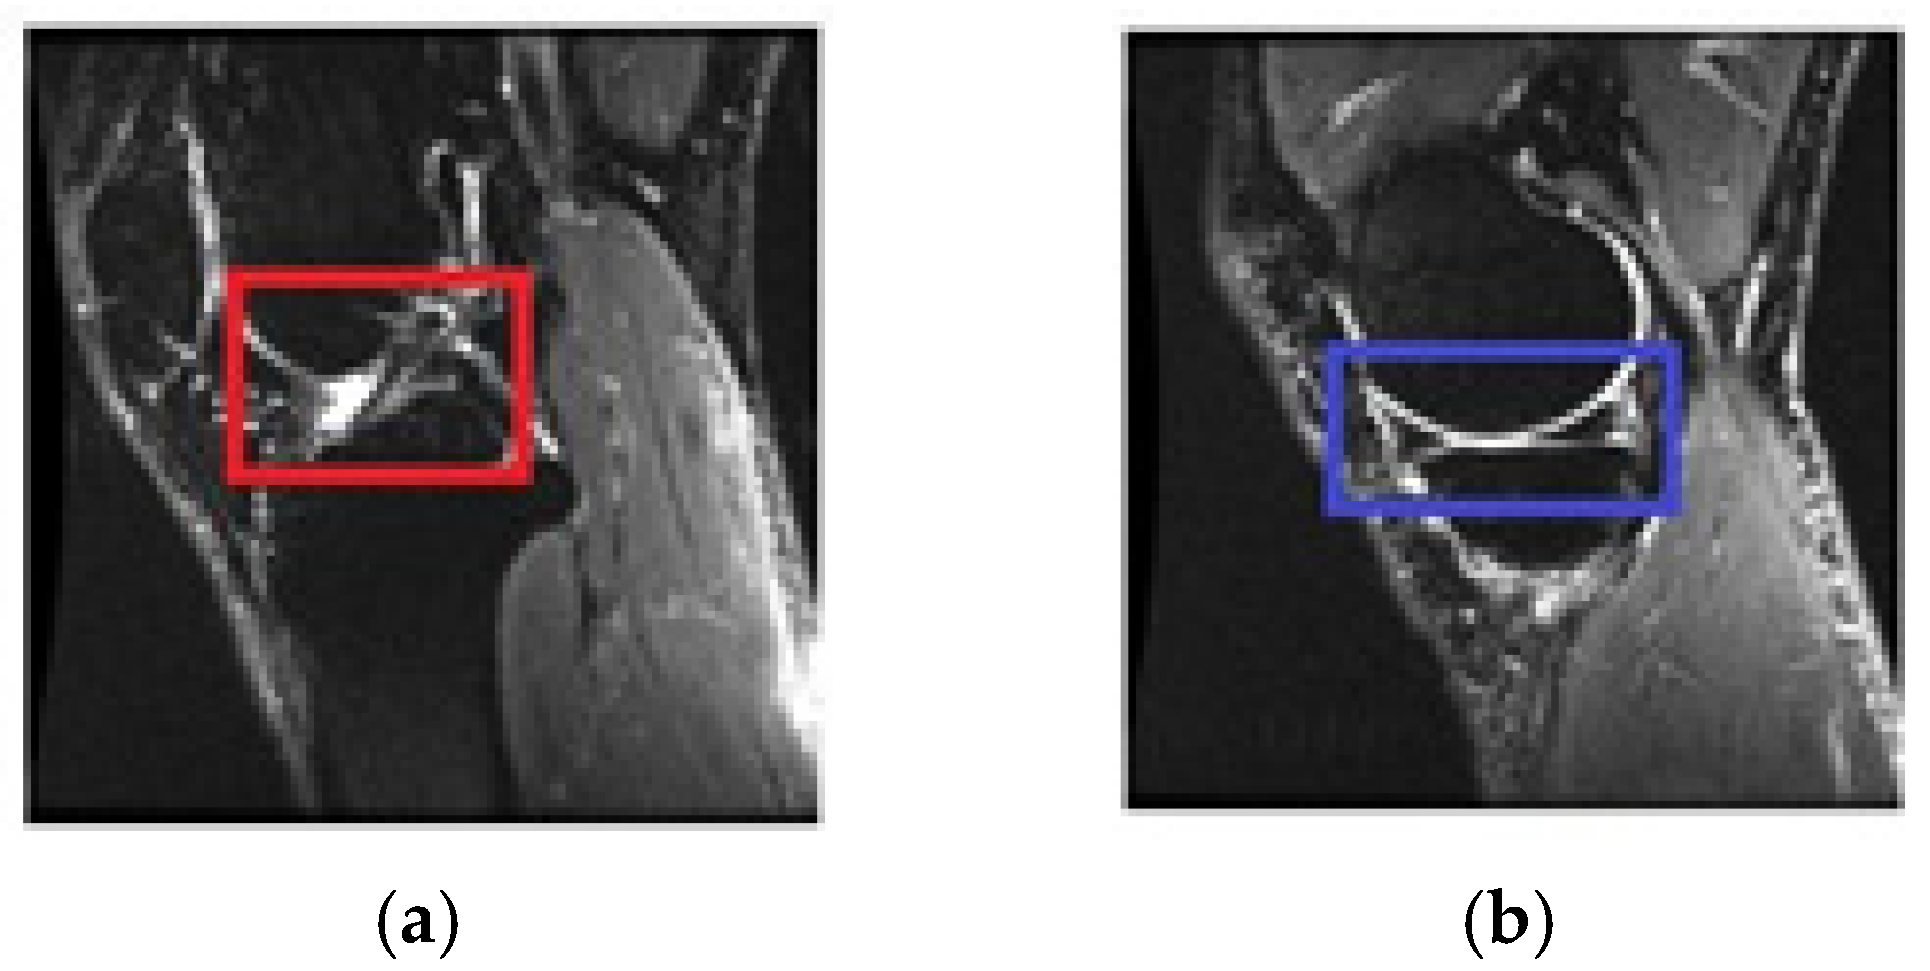

2.4. Selecting the Relevant Area

2.4.1. Selecting Relevant Areas on the Sagittal Axis

2.4.2. Selecting Relevant Regions on the Coronal Axis